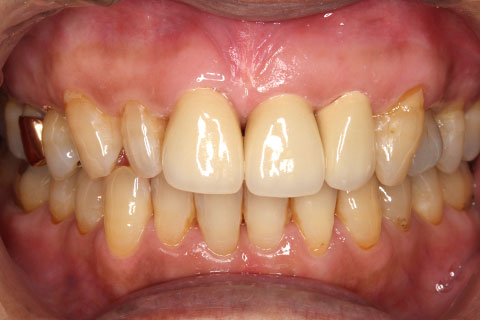

• オールセラミックの症例2

治療前

治療後

年齢・性別

45歳男性

治療期間

2ヶ月

抜歯

なし

治療費

70.4万円

備考

前歯8本の歯列不正によるセラミック治療

治療内容

歯質を削除し、セラミック冠をセメント合着

施術の副作用(リスク)

知覚過敏、歯髄炎、荷重負担